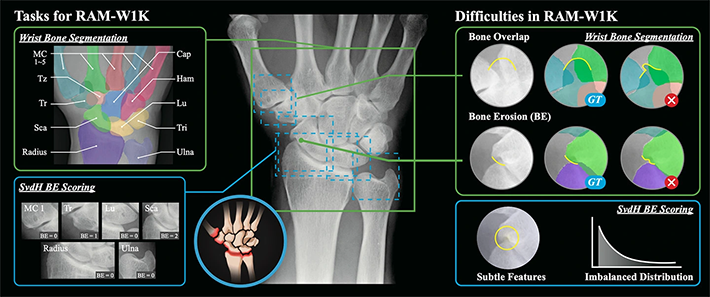

関節リウマチ(RA)は早期から手首関節を侵しやすい疾患であり、X線画像は広く用いられているものの、骨構造の複雑性や病的変形により、専門医による評価への依存度が高く、効率性に乏しいことがコンピューター支援診断(CAD)の発展を制限してきました。既存の公開データセットは、ピクセルレベルの分割アノテーションを欠くか、あるいは臨床的スコアが不足しており、RA特異的な研究ニーズを十分に満たしていませんでした。本研究では、RAに特化した世界初の手首関節X線画像多タスク大規模公開データセットRAM-W600を構築しました。本データセットは、手首関節骨のインスタンス分割及びSharp/van der Heijde(SvdH)骨侵食スコアという二つの主要タスクを網羅し、高品質なアノテーションとベンチマークを提供します。これにより、関節間隙狭小化の定量化や骨びらん検出といった多様な下流タスクを支援し、RA関連CAD研究のさらなる進展を後押しします。

本研究では、RAに特化した大規模公開データセット RAM-W600 を構築しました。本データセットは、4つの医療機関から収集した1,048枚の手首関節X線画像(388名の患者に由来)で構成され、そのうち618枚には骨単位のピクセルレベル分割アノテーションが、800枚には SvdH基準に準拠した骨侵食スコアが付与されています(図1)。研究チームはこれを基盤として多タスクベンチマーク実験を実施し、手首関節骨インスタンス分割及びBE分類に対する性能評価を行いました。評価には、Unet、Unet++、TransUNet、SwinUMambaなどの多様なディープラーニングアーキテクチャや、汎用モデル(SAM、MedSAM)を採用し、DSC、NSD、BACC、F1-scoreといった指標を用いて体系的に性能比較を行いました(図2)。

結果として、分割タスクでは教師ありモデルが総じて優れた性能を示し、特に SwinUMamba は DSC 97.75% という高い精度を達成しましたが、骨重なり部位や骨侵食領域では依然として顕著な精度不足が見られました。一方、汎用モデルのSAMは明らかに劣る結果となりました。BE分類タスクでは、モデル全体の性能は限定的であり、最高でも平衡精度は約52.6%にとどまり、F1-scoreも低値で、クラス不均衡に起因する感度不足が課題として確認されました。総じて、RAM-W600はRA手首関節画像に対する高品質な分割・スコアリング資源を提供するとともに、既存手法が複雑な臨床病変に直面した際の限界を浮き彫りにし、今後より堅牢なCAD技術の開発に向けた基盤を提示しています(図3)。

図3. 公開されたマルチタスクデータセットとAIベンチマーク。